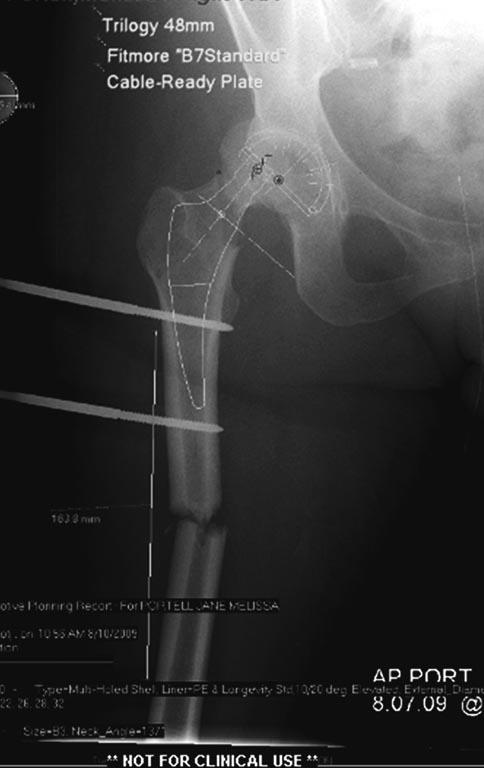

Из вариантов фиксации для проксимального и диафиза бедра выбрали

пластину, а по поводу артропластики остается вопрос между тотальным или

геми.

На всякий случай запланировали: короткий и длинный вариант ножки.

На 25 день с момента травмы операция на Jackson table с боковым обширным

доступом. Удаление стержней с местной обработкой. В тазобедренном

суставе удаление головки, на дне вертлужной впадины полная отслойка

хряща. Вертлужный компонент с одним винтом и короткая ножка -  Fitmore

press fit stem. На второй день однократно доза радиации для профилактики